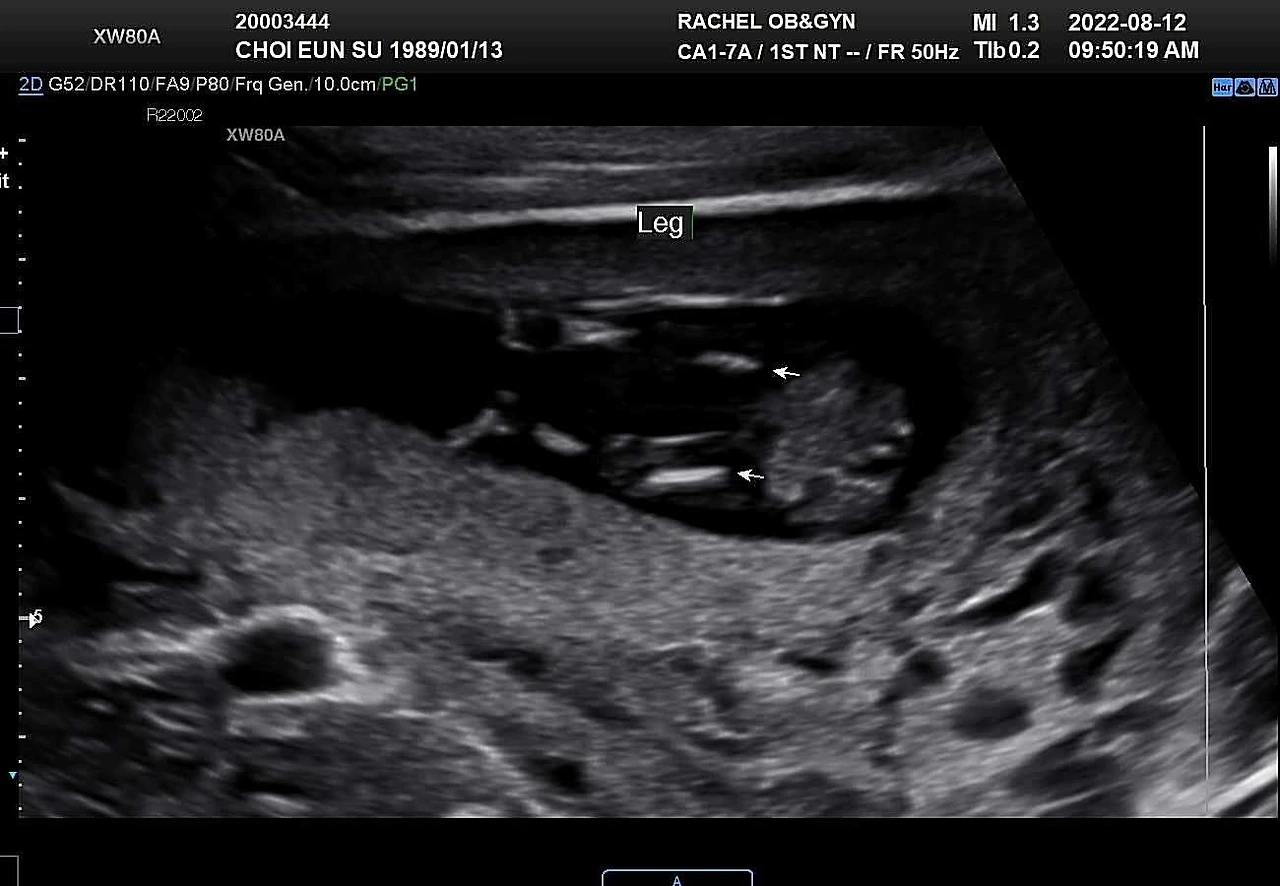

13주 1일. 1차 기형아 검사 결과를 들으러 병원에 갔다. 이제는 꽤 자란 모습이 눈에 보여서 심박수는 따로 재지 않고 열심히 뛰는 심장만 보여주셨다. 초음파를 대자마자 발도 구르고 손도 휘젓는 아기. 일주일 사이에 금세 자라 손가락 발가락도 더 잘 보이고, 코부터 턱까지 얼굴 옆 라인도 꽤 사람답게 보여서 기특했다.

*13주차 초음파 사진